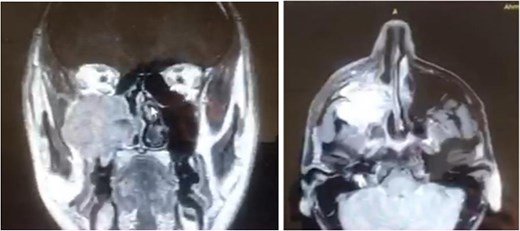

A 42-year-old male previously diagnosed with maxillary nasal sinus squamous cell carcinoma (SCC) was hospitalized for surgical treatment of recurrent infiltrating AC. The patient experienced three recurrences with the initial treatment approach for the cancer as SCC, a non-keratinizing variant. Complete excision and curettage of the lining mucosa were performed. In the second recurrence, the patient underwent additional curettage and subsequently revealed the absence of tumor residues from the mucosa and submucosa. However, the patient experienced a third recurrence with rapid growth and infiltration to the floor of the right maxillary sinus, filling the sinus space, infratemporal fossa, pterygopalatine fossa, cheek buccal area, and orbital floor. The imaging studies were preformed revealing a neoplastic lesion centered on the right maxillary sinus measuring 10 × 5 × 4.5 cm with a low T1 signal, heterogeneous iso T2/STIR signal, and intense heterogeneous post-contrast enhancement (Fig. 1). AC was recognized as stage II based on Yang’s et al. classification system [6]. Right Subtotal maxillectomy was performed through a Weber Ferguson incision with a Dieffenbach extension, and the infiltration areas were cleared. The excised tumor mass from the right maxillary sinus with labeled surgical margins (palate, orbital floor, buccal, and pterygoid surgical margins) was subjected to permanent paraffin evaluation (Fig. 2). The Right hemi-maxillectomy measuring 6 × 4.5 × 4 cm, revealed one canine, two molars, and two premolars found in the alveolar arch. An indefinite, grayish-white, infiltrating, fungating mass, approximately (⁓6 × 4 × 2.5 cm), was observed in the maxillary sinus. The cut surface of the mass was grayish-white and firm, with skeletal muscle attachment and noticeable infiltration into the underlying periosteum of the alveolar arch. Furthermore, labeled tumor tissue fragments measuring 4.7 × 2 × 2.5 cm and multiple smaller pieces collectively measuring 4 × 4 × 2 cm, showing similar characteristics, were stored in the same container. Microscopic examinations were performed at different magnifications. At a low magnification, the specimen revealed the presence of an infiltrative tumor with a biphasic pattern. The Islands and epithelial cell sheets are embedded in the fibrous stroma. The tumor islands exhibited a basaloid appearance with peripheral palisading, reverse polarity, and central stellate reticulum-like cells, reminiscent of ameloblastoma. However, these neoplastic epithelial cells exhibited moderate cytological atypia and increased mitotic activity, which suggests of malignancy (Fig. 3). Higher magnification shows tumor cells with enlarged, pleomorphic nuclei, prominent nucleoli, and eosinophilic cytoplasm. Frequent mitotic figures, including atypical forms, were also observed. Peripherally, tumor islands comprise cells with hyperchromatic elongated nuclei exhibiting focal palisading. The central cells were loosely cohesive and exhibited a stellate reticulum-like morphology. Additionally, focal areas of necrosis, hemorrhage, and keratinization were prominent in the tumor islands, and the surrounding stroma appeared desmoplastic and encompassed moderate chronic inflammatory infiltrates (Fig. 4). Additionally, diffuse infiltration of tumor into the adjacent tissues was observed, including bone and soft tissues, and is associated with perineural and lymphovascular invasion. Tumor extension in the orbital floor and buccal mucosal surgical margins was evident. In contrast, the palatal and pterygoid surgical margins are free of tumor involvement (Fig. 5). Overall, the morphological features were consistent with a diagnosis of infiltrating AC. Furthermore, immunohistochemistry assay was performed using a Ventana BenchMark GX Auto-stainer, employing the Ventana I View DAB detection system and Ventana monoclonal antibodies. The sections were stained for CK 5/6, P63, CK19, SOX-2, SOX-10, calretinin, and Ki67. The results revealed that the tumor basaloid epithelial component was strongly positive for P63 and showed weak heterogeneous positive staining for CK19, calretinin, and SOX-2 (Fig. 6). Conversely, it was negative for CK5/6 and SOX-10 staining. The Ki67 labeled index within the epithelial component was ⁓14%, whereas the mesenchymal component was 8%. The post-operative radiotherapy at 66 Gy was successfully administered. The patient is currently under observation, with careful follow-up.

Histopathological findings of specimen at higher magnification.